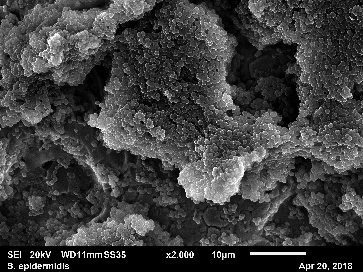

Improved understanding of the structure of biofilms and their function helps to develop treatments to avoid attachments and to eliminate biofilms from implant surfaces. The biofilms formed on different surfaces are assessed by comparing the antibiotic susceptibility of different strains and by examining their structures using metabolic and morphological methods.

- Débora C. Coraça-Huber 1, Lisa Kreidl , Stephan Steixner, Maximilian Hinz, Dietmar Dammerer, Manfred Fille: Research Article – Identification and Morphological Characterization of Biofilms Formed by Strains Causing Infection in Orthopedic Implants. Pathogens 2020, 9, 649; doi:10.3390/pathogens9080649